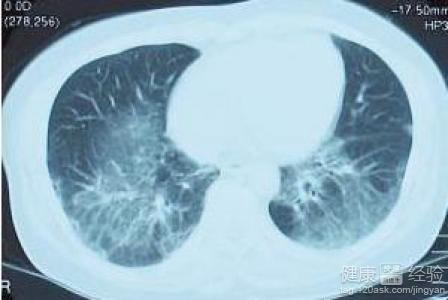

间质性肺炎是一种涉及肺间质组织的炎症性疾病,其病因复杂多样,包括环境因素、遗传因素、免疫因素等,临床表现主要为咳嗽、呼吸困难、乏力等,严重者可导致肺功能衰竭,根据病理变化,间质性肺炎可分为多种类型,如特发性肺纤维化(IPF)、结缔组织病相关间质性肺疾病等。